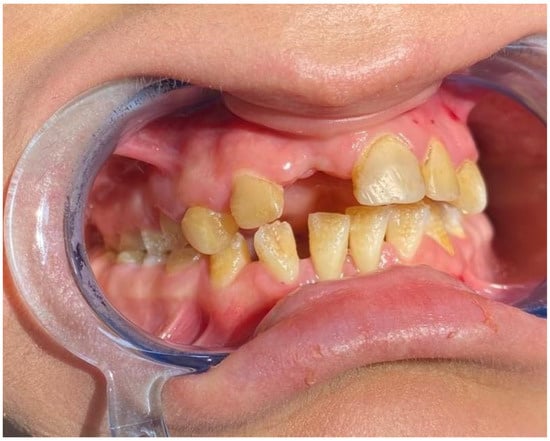

| Enamel hypoplasia | 0 | 1 | 0 | 26 | |

| Extracted tooth | 0 | 1 | 17 | 26 | |

| Periodontal disease | 0 | 1 | 17 | 26 | |

| Maxillary atrophy | 0 | 0 | 18 | 26 | |

| Vestibular sulcus insufficiency | 0 | 0 | 19 | 26 | |

| Restorative treatment history | 0 | 1 | 2 | 26 | |